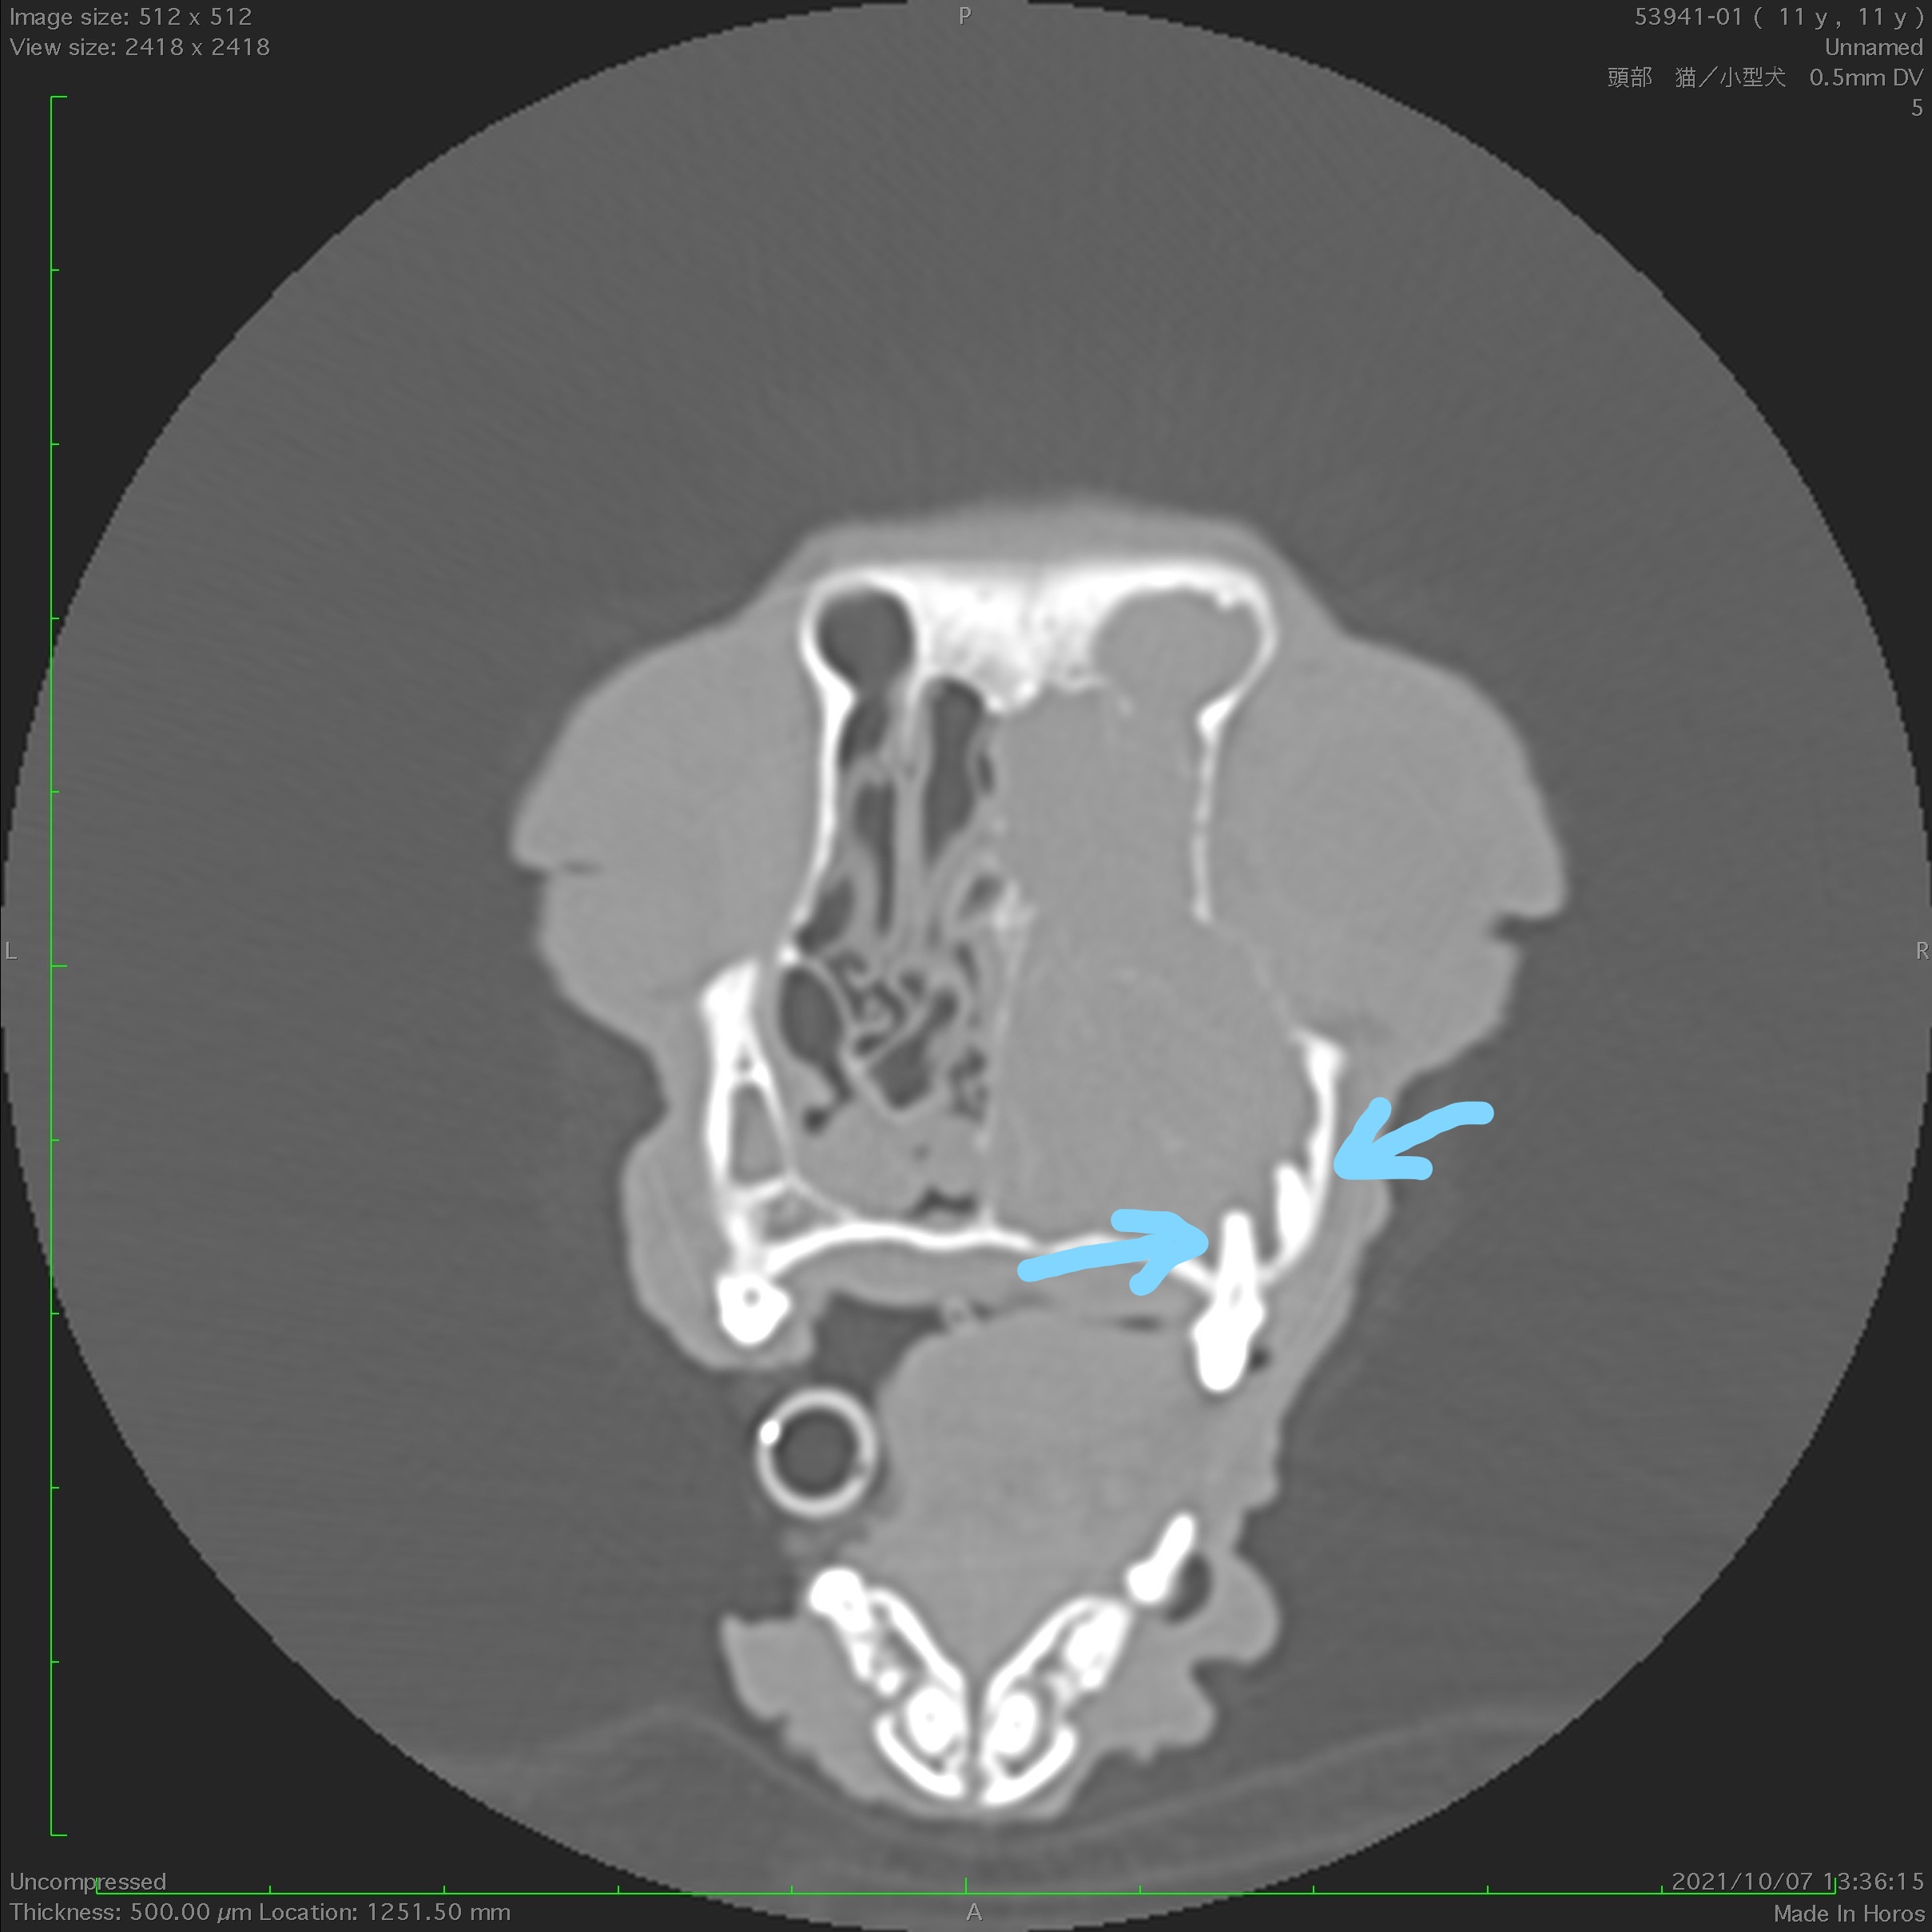

(CT像)矢印部分の歯根と鼻腔が連続しており、片側全体が膿瘍で満たされている